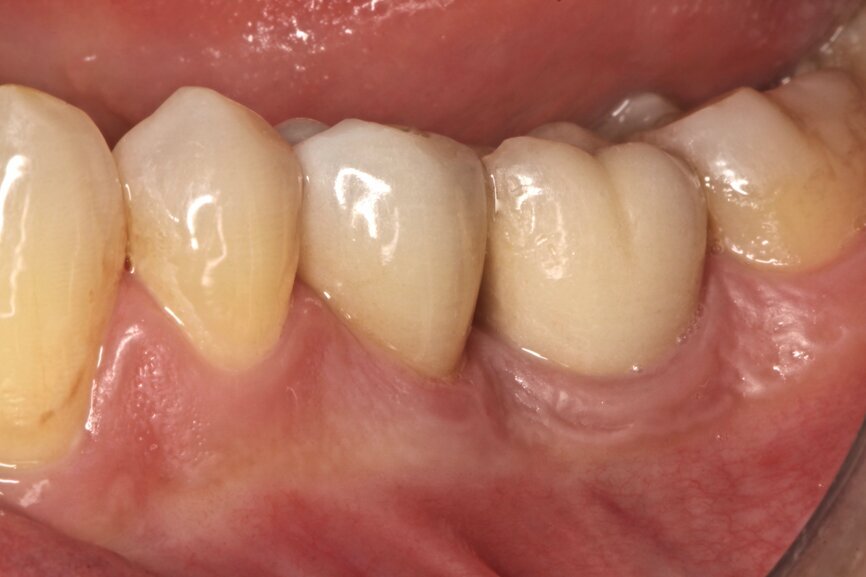

A healthy, non-smoking, 40-year-old male patient presented with a mandibular left first premolar with a fractured root. The root had previously been treated endodontically, three years before suffering a bone level transversal fracture (Figs.1a & b). The patient had already received several implants to replace some of his lost teeth over the previous nine years. The missing mandibular premolar could be easily seen and was one of his complaints. The patient had moderate aesthetic expectations, high functional demands and little time to come to the appointments.

Fig. 1a: Initial situation: apical radiograph (a), intra-oral view (b) and CT scan (c).

Fig. 1b: Initial situation: apical radiograph (a), intra-oral view (b) and CT scan (c).